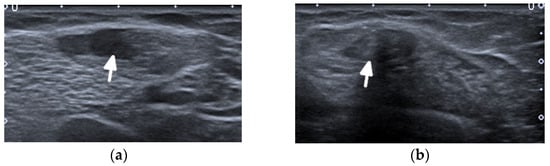

Ultrasound (US) and MRI show effusions and synovial and/or tenosynovial hypertrophy. Power and color doppler US, including newer microvascular techniques and contrast-enhanced MRI, show active synovial inflammation [] (Figure 1). Compared with RA, the swelling caused by effusion and synovial hyperplasia and vascularity in SLE arthritis is relatively light []. Pathology reveals widespread vasculitis affecting capillaries, arterioles, and venules, and—unlike pannus in RA—villous hypertrophy of the synovium covered by fibrin and low-grade lymphoplasmacytic inflammatory cell infiltrates in the subintima [].

Figure 1.

A 34-year-old female with systemic lupus erythematosus. (a) Posterior–anterior and oblique (b) radiographs of the bilateral hands show a non-united fracture of the right scaphoid waist, with increased sclerosis of the proximal pole and proximal waist consistent with osteonecrosis (arrow), possibly steroid-induced, and with no additional deformities. (c) Long-axis power Doppler ultrasound images at the volar aspect of the ring finger, (d) dorsal ulnar aspect of the wrist, and (e) volar aspect of the wrist show increased synovial vascularity involving the ring finger in (c) and the 6th extensor compartment tendon sheath in (d), consistent with tenosynovitis (arrows). Synovitis at the volar aspect of the radiocarpal and midcarpal joints without erosive bone changes is seen in (e) (arrowheads).